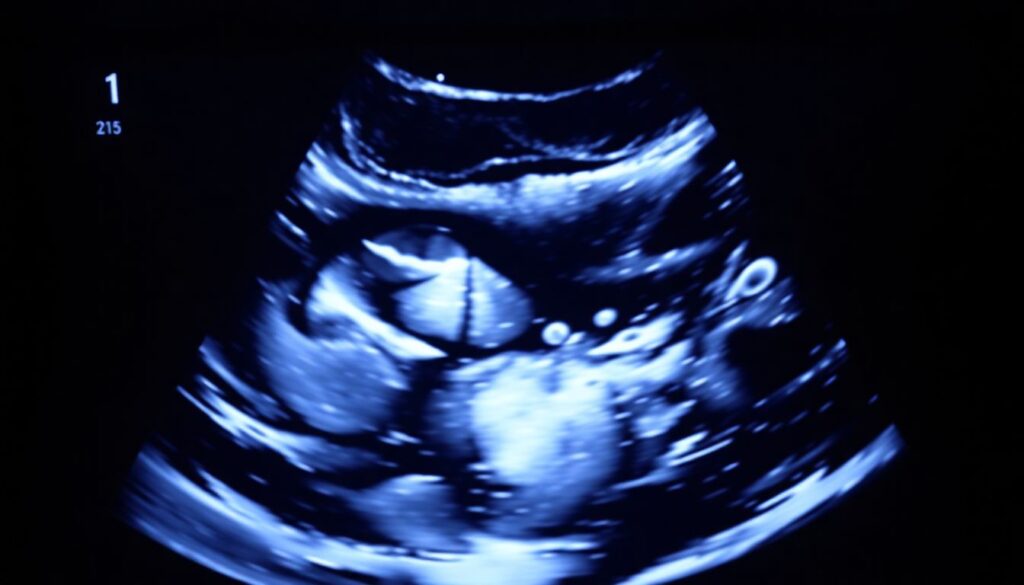

4. Состояние органов: Врач может оценить сердце, почки, желудок, мозг, позвоночник и другие структуры.